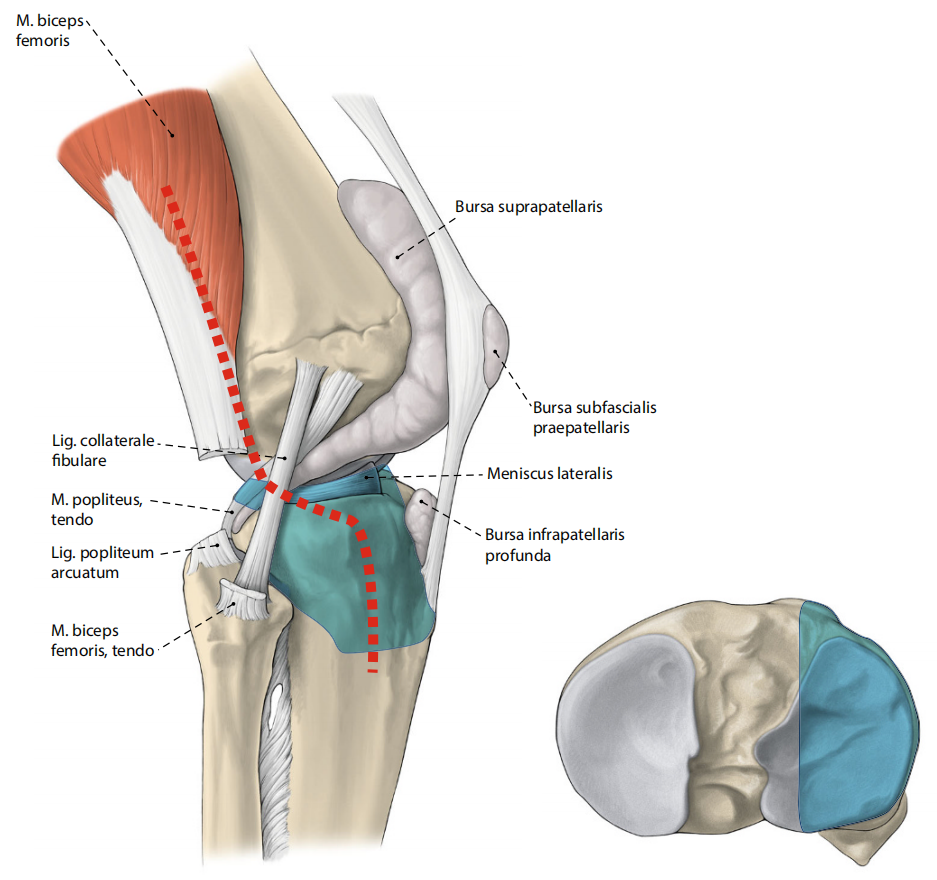

图8. 2010年Frosch提出的后外侧入路。适应症:累及后外侧柱的外侧柱骨折,或需支撑钢板固定的孤立后外侧柱骨折。患者取侧卧位,皮肤切口始于关节线上方3厘米,沿腓骨向远端延伸。关节切开术可于髂胫束后缘与外侧副韧带前缘之间进行,由此显露Krause分类的ALZ、ALL、PLZ、PLL区域。显露腓总神经后,可在以下结构间建立肌间隙:内侧为腓肠肌外侧头,前上内侧为腘肌,下方为比目鱼肌,外侧为股二头肌肌腱,从而实现后外侧骨折的暴露(蓝色标记区域)。除翻修病例外,近端腓骨截骨通常无需实施。